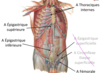

vascularisation du membre supérieur, thorax et abdomen Flashcards